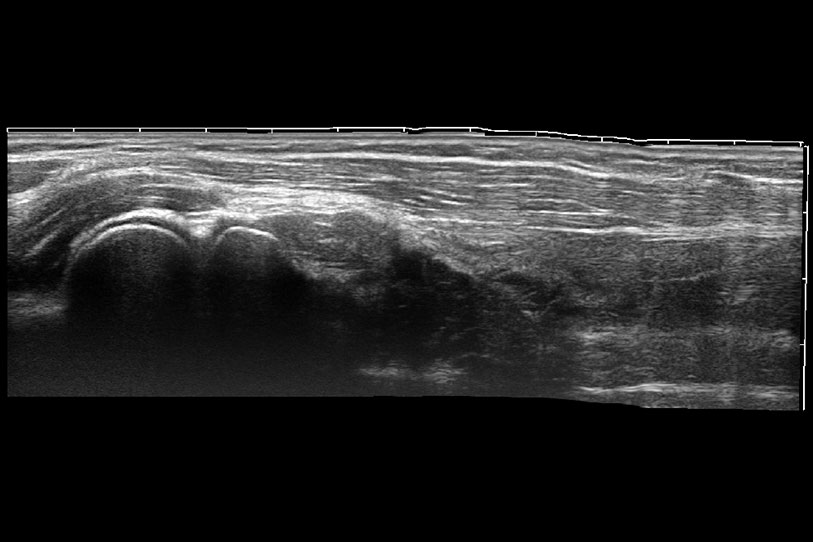

通過色彩血流和實(shí)時(shí)寬景相結(jié)合,可觀察到完整的靜脈或動脈的血流,方便醫(yī)生檢查。實(shí)時(shí)掃查過程中,如有任何操作失誤也可以很容易地進(jìn)行回掃擦除,而不會中斷掃查。